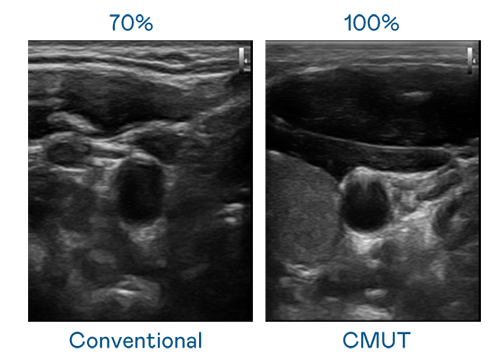

CMUT 技术是一种用电容式微机电元件来产生超音波讯号的技术。与传统 PZT 压电式技术相比,CMUT 频宽增加 30%,更宽频的超音波讯号让影像解析度大幅提升,是实现高影像品质医疗超音波扫描、促进精准医疗发展的关键技术。

超音波影像的解析度高低,首先取决于探头能发出的讯号频宽。英国正版365 CMUT 可提供高清晰的超音波讯号,提供高频宽、高灵敏度、影像纹理细节更高的超音波影像,协助医护人员缩短影像判读时间及利用精准的医疗影像进行诊断。